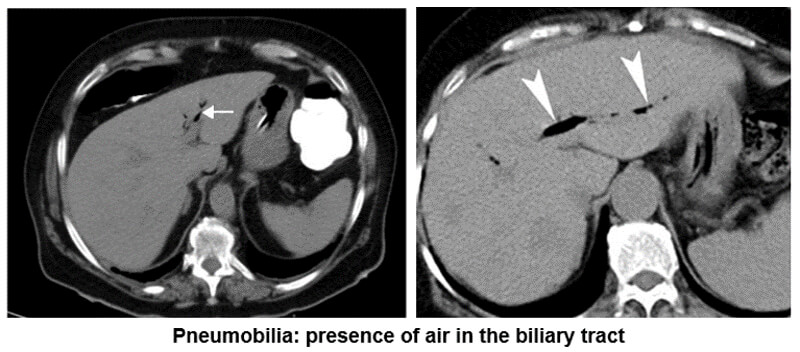

Biliary Tract

This example shows us the presence of air in the biliary tract known as pneumobilia. Notice the white arrows pointing out the air.